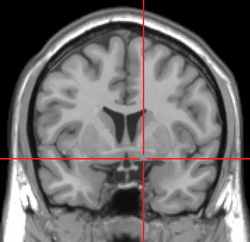

MRI showing a coronal plane of the head with marks showing the location of the substantia innominata, the region in which the nucleus basalis is found. | |

The NBM is inferior to the globus pallidus and within an area known as the substantia innominata. The NBM is immediately inferior to the anterior commissure and superior and lateral to the anterior portion of the hypothalamus.